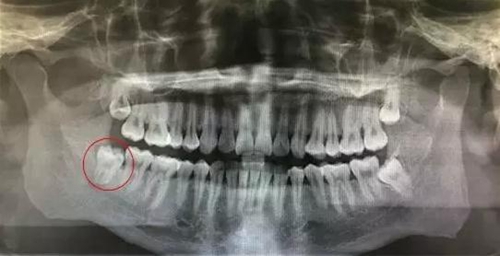

圖2.局部放大的影像學(xué)檢查:48雙根環(huán)抱型,遠中有牙囊影。